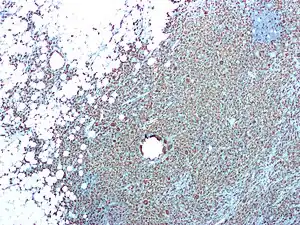

Pielonefrite

Pielonefrite é a inflamação do rim, geralmente causada por uma infeção bacteriana.[3] Os sintomas mais comuns são febre e sensibilidade no ângulo costovertebral.[2] Entre outros possíveis sintomas estão náuseas, ardor ao urinar e micção frequente.[2] Entre as possíveis complicações estão pus em redor do rim, sepse e insuficiência renal aguda.[3]

A pielonefrite é quase sempre causada por uma infeção bacteriana, sendo cerca de 80% dos casos causados por Escherichia coli e Enterobacter.[6][2] Entre os fatores de risco estão as relações sexuais, antecedentes de infeções do trato urinário, diabetes, problemas estruturais no trato urinário, obstrução do uréter e uso de espermicidas.[2][3] O mecanismo de infeção mais comum tem origem em infeções ascendentes com origem no próprio sistema urinário.[2] Em casos pouco comuns, a infeção tem origem na corrente sanguínea.[1] O diagnóstico geralmente baseia-se nos sintomas e é complementado por análises à urina.[2] Quando o tratamento inicial não surte efeito, pode ser necessária a realização de exames imagiológicos.[2]